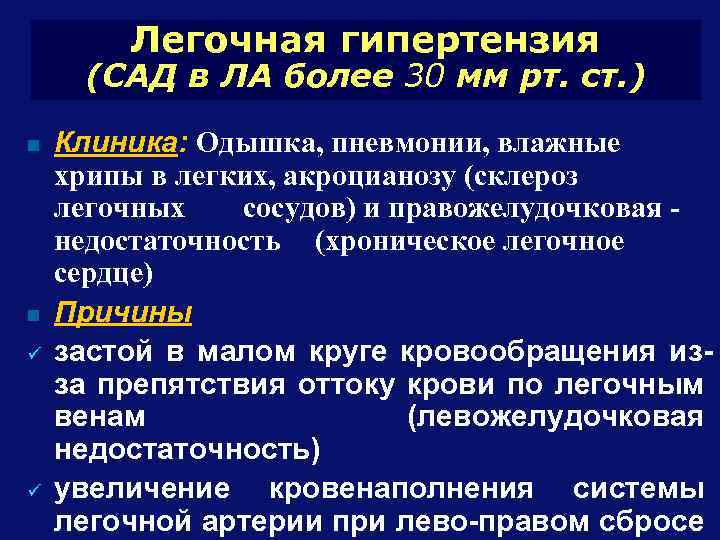

Легочная гипертензия (САД в ЛА более 30 мм рт. ст. ) n n ü ü Клиника: Одышка, пневмонии, влажные хрипы в легких, акроцианозу (склероз легочных сосудов) и правожелудочковая недостаточность (хроническое легочное сердце) Причины застой в малом круге кровообращения изза препятствия оттоку крови по легочным венам (левожелудочковая недостаточность) увеличение кровенаполнения системы легочной артерии при лево-правом сбросе